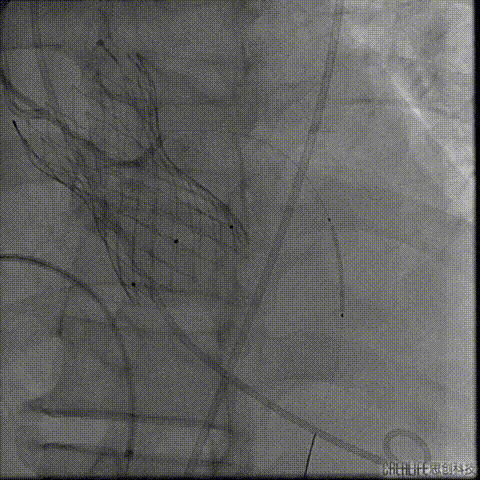

预扩主动脉瓣

左冠血流受到影响

予ECOM支持